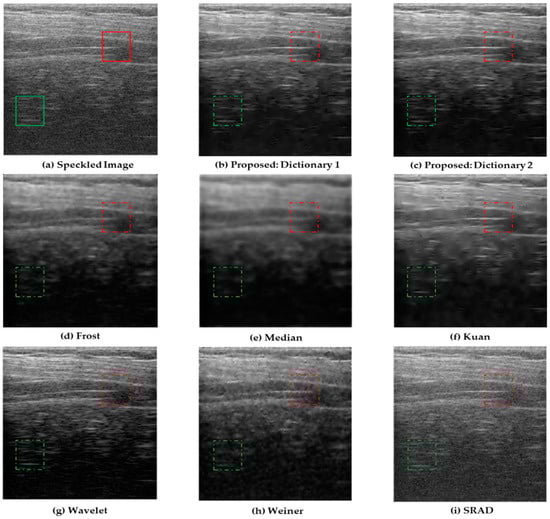

4.2. Clinical Liver Ultrasound Images

| Frost | 28.966 | 0.822 |

| Median | 25.497 | 0.659 |

| Wavelet | 27.772 | 0.782 |

| SRAD | 28.766 | 0.813 |

| Kuan | 28.279 | 0.801 |

| Weiner | 29.218 | 0.834 |

| Proposed: Dictionary 1 | 30.334 | 0.901 |

| Proposed: Dictionary 2 | 30.807 | 0.926 |